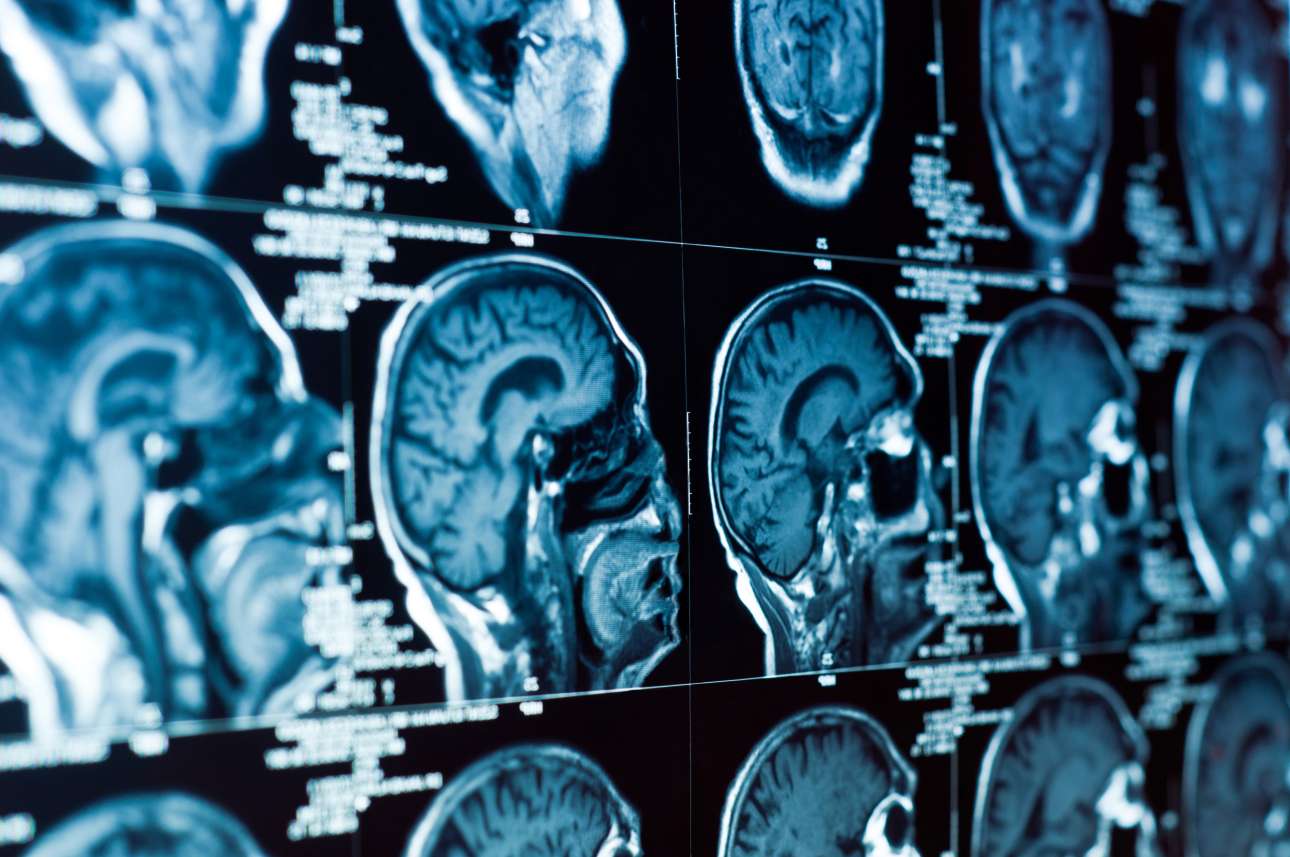

Μια ηλικιωμένη γυναίκα στη ρωσική Απω Ανατολή έχει ζήσει όλη της τη ζωή με μια βελόνα, μήκους τριών εκατοστών, στον εγκέφαλό της, όπως αποκάλυψε πρόσφατη αξονική τομογραφία στην οποία υπεβλήθη.

«Η βελόνα τρύπησε τον αριστερό βρεγματικό λοβό, αλλά δεν είχε το επιθυμητό αποτέλεσμα. Το κορίτσι επέζησε», είπαν οι γιατροί, προσθέτοντας ότι η ασθενής δεν είχε παραπονεθεί ποτέ για πονοκεφάλους και η υγεία της δεν είναι σε κίνδυνο. «Η κατάστασή της παρακολουθείται από τον αρμόδιο γιατρό», κατέληξαν.